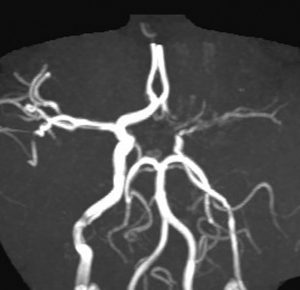

脳血管障害

- 放射線被爆で脳血管の内膜が肥厚して,動脈が狭くなる(狭窄)ことによって生じます

- ウィリス動脈輪というところが照射範囲に含まれた時に生じます

- 頭蓋咽頭腫,胚細胞腫瘍,ジャーミノーマなど鞍上部に発生する腫瘍への照射後に多いのですが,これはウィリス動脈輪が被曝するからです

- 脳梗塞を生じることがあります

- もやもや病という病気に似たような内頚動脈狭窄症が多いでしょう

- 低年齢で放射線治療を受けた子どもに多いです

- 10歳以下で放射線治療を受けた子どもに多いです

- ウィリス動脈輪のに40グレイくらいの照射が入ると頻度が高くなるでしょう

- 放射線治療後10年以内くらいに生じます,でも脳梗塞となり発症するのはまれです

- ですから,脳腫瘍の放射線治療後10年くらいまでは,MRAという検査で動脈が狭くなっているかどうかをみる必要があります

- でも実際にはおよそ5年以内で,動脈狭窄が生じるかどうかはわかります

生後7ヶ月で髄芽腫になりました。手術全摘出して,化学療法して,3歳になる頃に放射線治療をしました。大脳には18グレイが入っています。6歳の時に前頭部に放射線誘発髄膜腫を生じました。その後に,左内頚動脈が狭窄して片側のモヤモヤ病(ウィリス動脈輪閉塞症)になりました。脳血流は保たれていて20年以上見ていますが脳梗塞にはなりませんでした。照射時の年齢が幼いとかなりの低線量でも脳動脈閉塞は生じます。